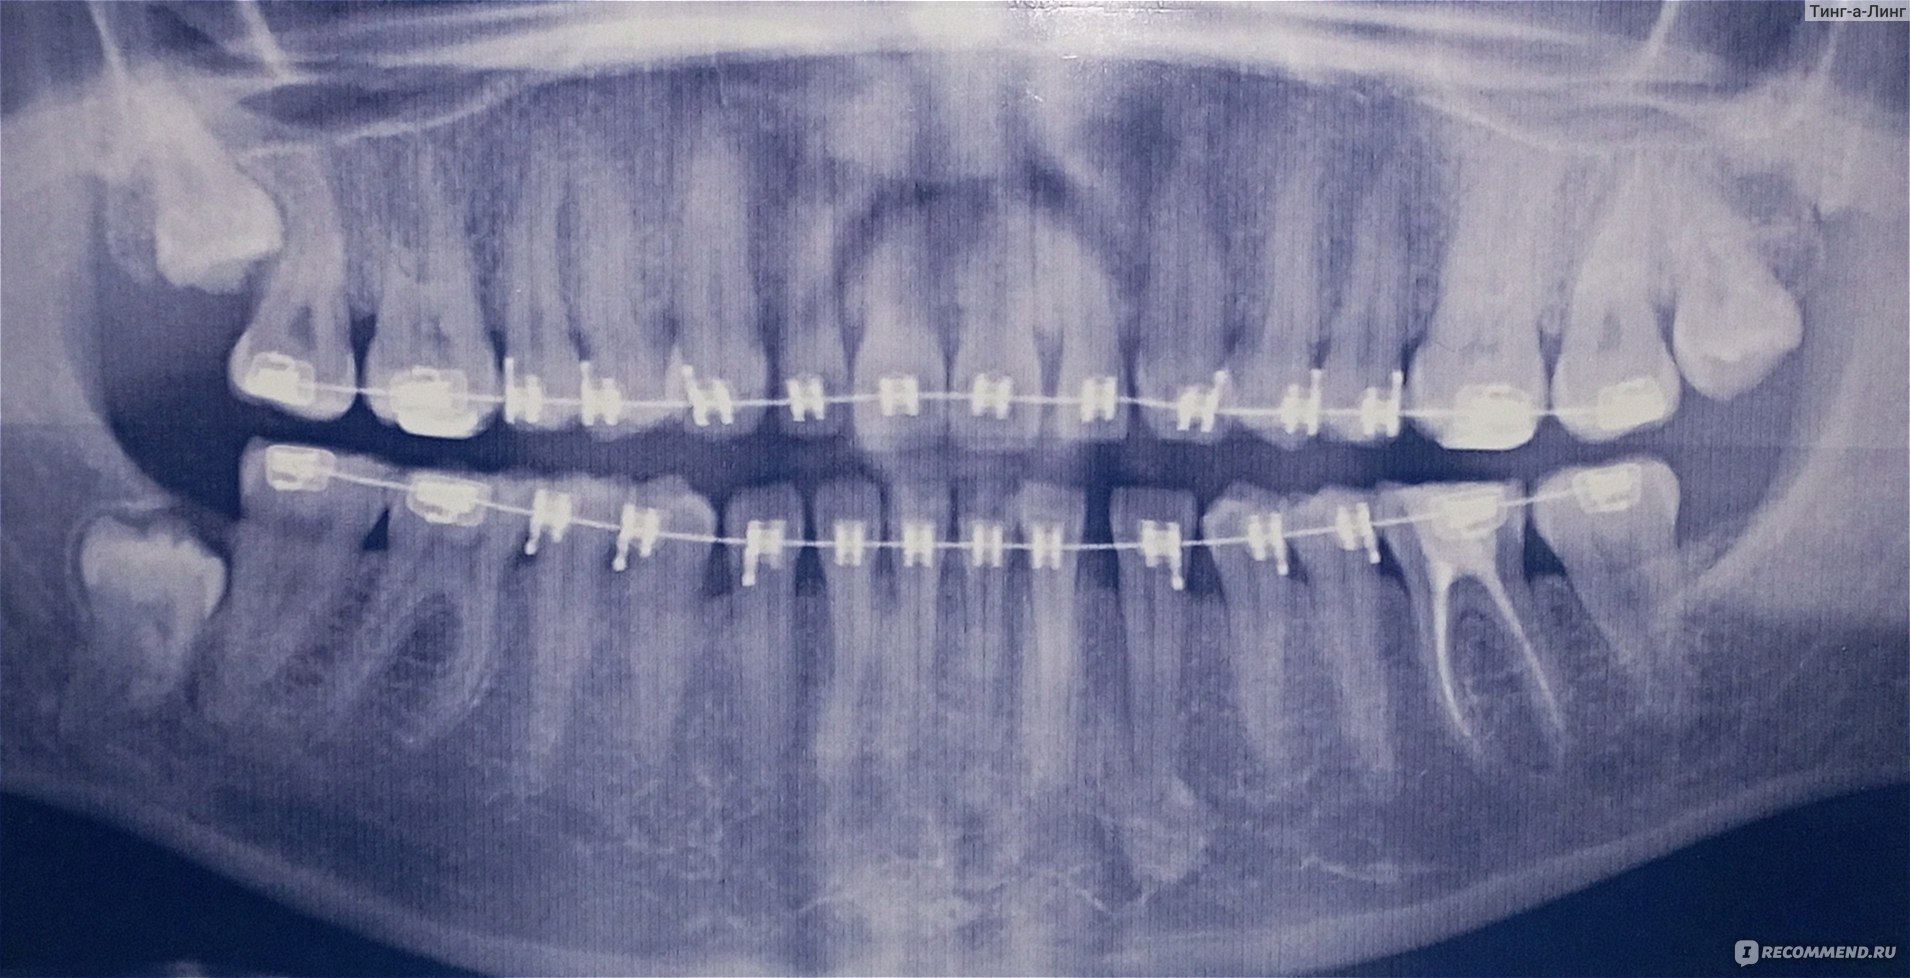

Дентальные снимки и диагностика кариеса